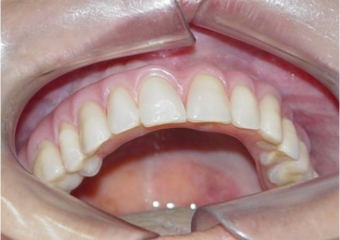

Prótese fixa em resina sobre implantes, do caso terminado em Dezembro de 2007